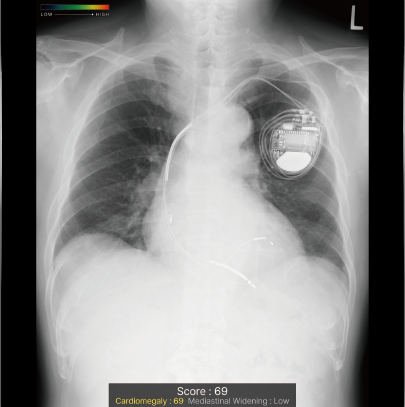

撮影した胸部単純X線画像を自動解析。対象の10所見が疑われる領域を検出しマーキング。

従来の結節/腫瘤影、浸潤影、気胸に加え、無気肺、石灰化、瘢痕、胸水、気腹、心拡大、縦隔拡大の10所見に拡張。

CXR-AIDが候補領域の解析をおこなったのち、0~100に応じた確信度を色分けして表示。

検出領域ごとに所見名を表示します。

対象所見のそれぞれの確信度の最大値が所見ごとに個別に表示されます。

ヒートマップと輪郭の表示は3パターンから選択可能です。